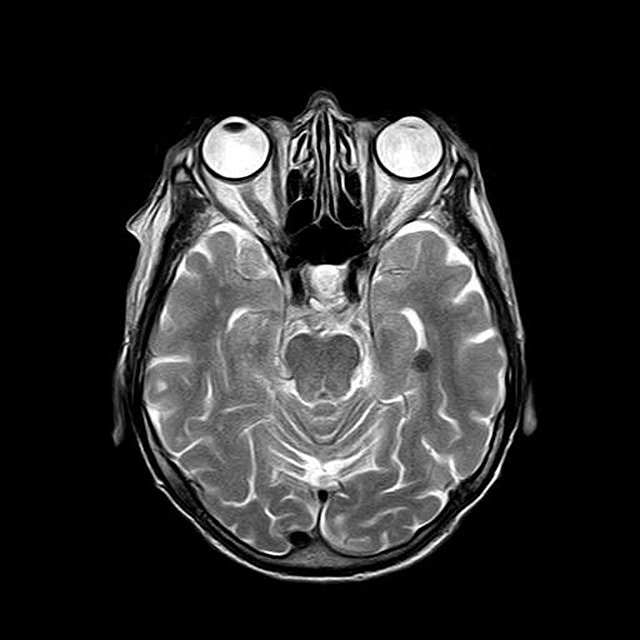

각각의 pixel들로 구성된 자기 공명영상은 가로, 세로에 어떻게 분포

되어 있느냐에 따라 저 분해능 영상, 고 분해능 영상으로 구별할 수 있다.

이것은 128 ×128, 256 ×256, 512 ×512등의 수치로 표시되고 있는데 이것

을 우리는 matrix size라고 부른다. 만약 일정한 FOV(Field Of View)가

주어진 상태에서 matrix size는 pixel size와 공간 분해능을 결정하며, 각

각의 pixel size는 FOV/matrix size라는 공식으로 얻을 수 있다. 여기서

pixel은 picture element의 약자이고 Voxel 또는 volume element의 2차원

적 표시라고 할 수 있다. 즉 영상은 pixel들의 집합체이며, 이러한 pixel들

은 영상을 구성함에 있어 신호강도와 위치를 결정해 주게 된다. 만약 영

상에서 검은 부분과 밝은 부분이 있다면 이것은 spin에 의해 방출되는 신

호 강도와 관련이 있게 되는데, 검은 부분은 낮은 신호강도를 지닌 pixel들

로 표시되고 밝은 부분은 높은 신호강도를 지닌 pixel들로 나타날 것이다.

또한 자기공명 영상에서 pixel의 위치는 경사자계에 의해서 결정되고 이것

은 pulse sequence에 의해 T1, T2 , PD(SD)의 대조도로 구분된다.